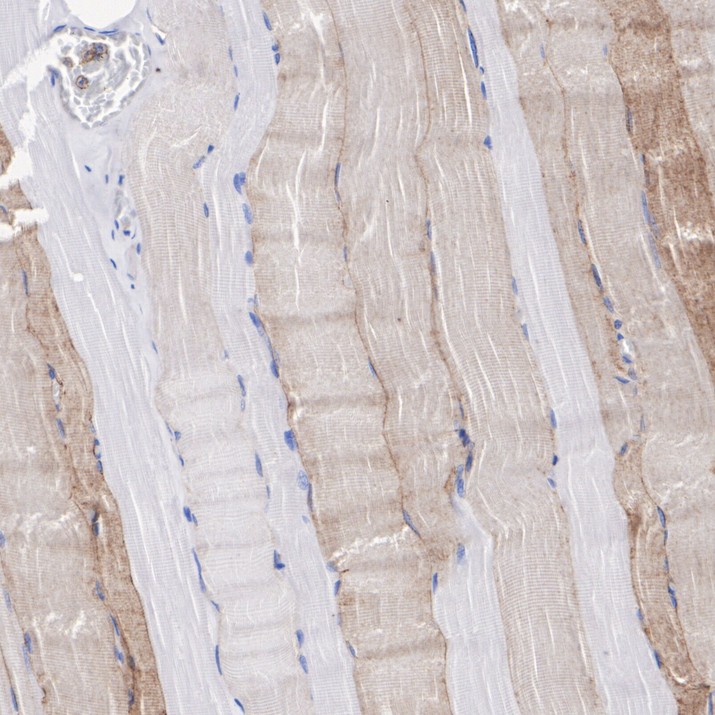

HA751115_5.jpg Fig5: Immunohistochemical analysis of paraffin-embedded human skeletal muscle tissue with Rabbit anti-SLC16A3 / MCT 4 antibody (HA751115) at 1/1,000 dilution.

The section was pre-treated using heat mediated antigen retrieval with Tris-EDTA buffer (pH 9.0) for 20 minutes. The tissues were blocked in 1% BSA for 20 minutes at room temperature, washed with ddH2O and PBS, and then probed with the primary antibody (HA751115) at 1/1,000 dilution for 1 hour at room temperature. The detection was performed using an HRP conjugated compact polymer system. DAB was used as the chromogen. Tissues were counterstained with hematoxylin and mounted with DPX.